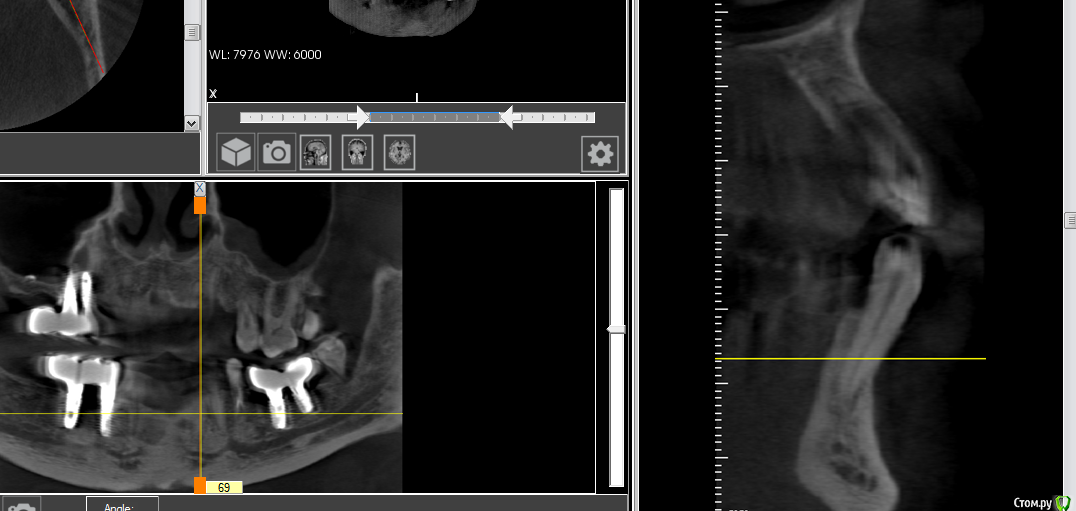

gum Опубликовано 3 декабря, 2020 Поделиться Опубликовано 3 декабря, 2020 Здравствуйте. Ситуация следующая: у 2 пациентов за последний год обнаружил продолжение нижнечелюстного нерва, ранее не сталкивался с таким. У одного во фронтальном отделе стояли имплантаты, через год началось отторжение, в апикальной части, сначала один, потом и второй.при повторной попытке установить имплантаты, анестезия действовала ровно полчаса, ставили в 2 этапа, первый день, разрез и ложе, во второй закрутил и зашил, зашивал уже с болями. Далее боли постоянные в течении 2 недель и сильные, итог все убрали, все прошло.Второй пациент при попытке установить имплантаты по месту 44,45 анестезия работает не более 20 минут, на этапе сверления боли, мандибулярную "постеснялся" делать после первого пациента.Оба пациента часто нервничают, в силу профессии.Вопрос как вести таких пациентов? Почему такая реакция, в 1 случае 6 имплантатов ставили без проблем, а с фронтальными сложности. Сможет ли невролог помочь? (На консультацию к нему направил).Кто сталкивался с подобным? Ссылка на комментарий

колесников Опубликовано 3 декабря, 2020 Поделиться Опубликовано 3 декабря, 2020 Интрасептальные ответвления n.alv. Защемление их приводит к таким последствиям. Внимательно смотреть клкт,тщательно планировать позиционирование импланта Ссылка на комментарий

shy Опубликовано 3 декабря, 2020 Поделиться Опубликовано 3 декабря, 2020 резцовые петли , 2 варианта в этой ситуации1)полностью спланировать позицию имплантата что бы обойти их2)полностью пересечь их , если 'недорезать' могут начаться боли в этой области и тут либо доставать имплантат либо ждать пока пройдет (а может и не пройдет)Невролог чем поможет? это анатомические особенности . Ссылка на комментарий

Александр07 Опубликовано 26 декабря, 2020 Поделиться Опубликовано 26 декабря, 2020 Согласен с тем что возможна психосоматика, и седация как вариант Как альтернатива помощь Невролога в плане подготовки Пац к операции- прием седативных препаратов курсом поможет снять стресс и напряжение как и с работой связанное так и с повторным вмешательством По срезам что скинули довольно глубоко расположен нерв и обойти должно получится Ссылка на комментарий